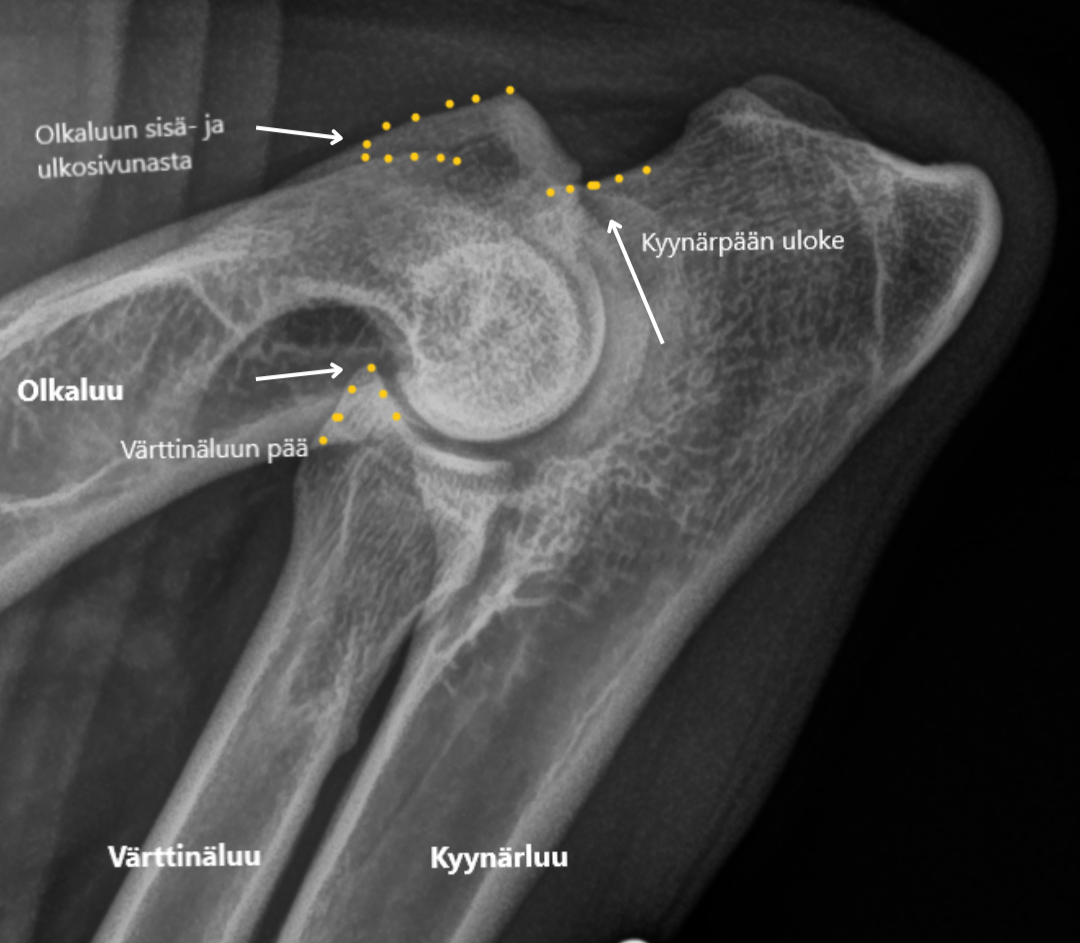

Kyynärniveldysplasia (ED)

Kyynärniveldysplasia on kasvavan koiran eturaajojen kehityshäiriö, joka voi johtaa nivelrikkoon. Se voi ilmetä ontumisena, jäykkyytenä tai liikkumisen epäsymmetriana. Perinnöllisyyden lisäksi kasvuajan ruokinta, liikunnan määrä ja kuormitus vaikuttavat sairauden kehittymiseen. Varhainen toteaminen ja oikeanlainen hoito voivat parantaa koiran elämänlaatua merkittävästi.

Kuvassa on terve kyynärnivel, keltaisella on esitetty ne kohdat, joihin nivelrikkoa yleisimmin kehittyy.